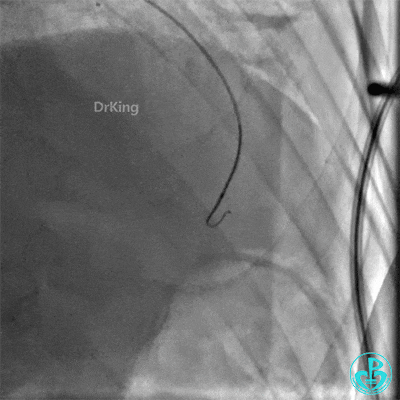

右桡动脉入路6F EBU 3.75指引导管到位,Corsair 150微导管辅助,Sion导丝尝试通过侧支。

Corsair微导管跟进困难,换Finecross 150微导管,通过侧支到达前降支闭塞远端血管真腔。